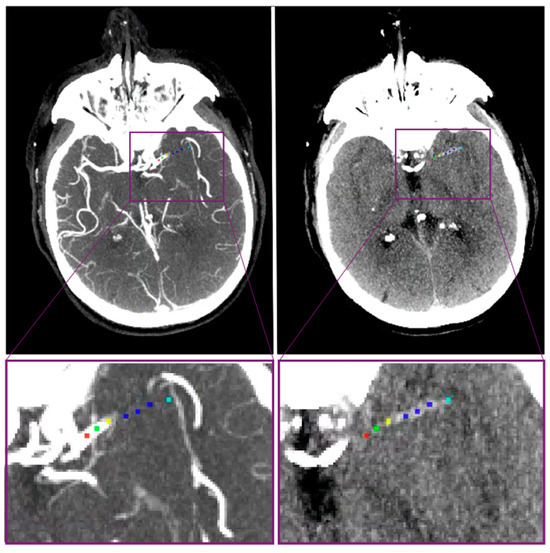

2.3. Patient and Thrombus Imaging Characteristics

2.3.1. Regional Database

2.3.2. MR CLEAN Database